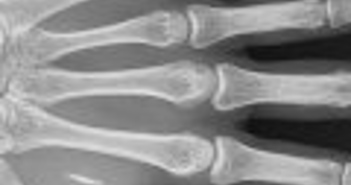

MIT研究チームが4ヶ月間、54人の脳をスキャンして驚愕の事実を発見した。

ChatGPTユーザーの脳内神経接続が47%も減少していたのだ。79あった接続が42まで崩壊。パソコンなら「故障」と呼ぶレベル😱。

「ChatGPTで脳が壊れる」というものです。脳波測定という手法で4か月間にわたって脳の活動を詳しく分析しました。「ChatGPT使用グループ」「検索エンジン使用グループ」「何も使わないグループ」に分けてエッセイを3回作成させたところ、“脳の連結性は、外部支援の量に応じて系統的に縮小するという確固たる証拠を示した”というのです。

「ChatGPT使用グループ」の脳の領域は神経連結性が弱いままだったのに対し、「何も使わないグループ」では記憶想起能力が高く、後頭葉・頭頂葉および前頭前野の広範なノードの再関与が見られたのです。要するに、何も使わずにエッセイを作成していた人たちが4回目にChatGPTを使用したところ、脳の神経活動が劇的に活発化したというのです。